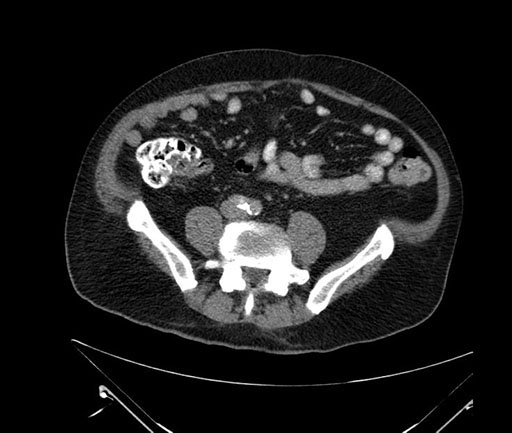

Whipple (pancreaticoduodenectomy) [case 7]

Look through the patient's CT scan to identify any areas of concern for the necessary procedure.

Axial - stented

Imaging analysis

Based on your CT findings, which issue(s) would give reason for "planned slowing down moment(s)" in this case?

Considering a standard Whipple procedure, what step(s) of the operation would you do differently in this case?